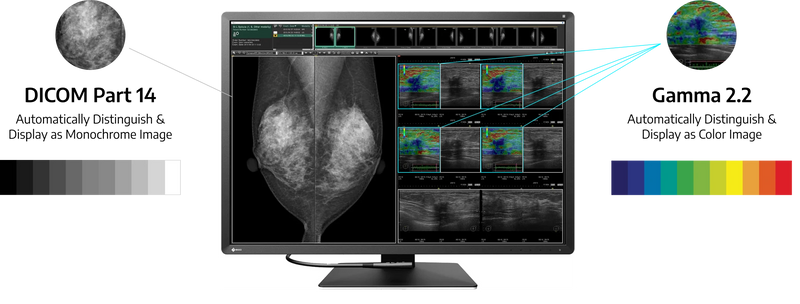

Εμφανίστε τόσο μονόχρωμη όσο και χρώμα

Η υβριδική λειτουργία Gamma PXL διακρίνει αυτόματα το Pixel Pixel από το Pixel, δημιουργώντας μια υβριδική οθόνη όπου κάθε εικονοστοιχείο έχει βέλτιστη κλίμακα γκρι. Αυτό τελικά βελτιώνει την αποτελεσματικότητα επιτρέποντας την προβολή μονόχρωμων και έγχρωμων εικόνων σε μία οθόνη.

Κάντε την ακριβή διάγνωση

Το Eizo μετρά και θέτει κάθε τόνο του γκρι για να δημιουργήσει μια οθόνη συμβατή με το DICOM Part 14. Αυτό εξασφαλίζει την πιο συνεπή δυνατή σκίαση, επιτρέποντας την πιο ακριβή διάγνωση.